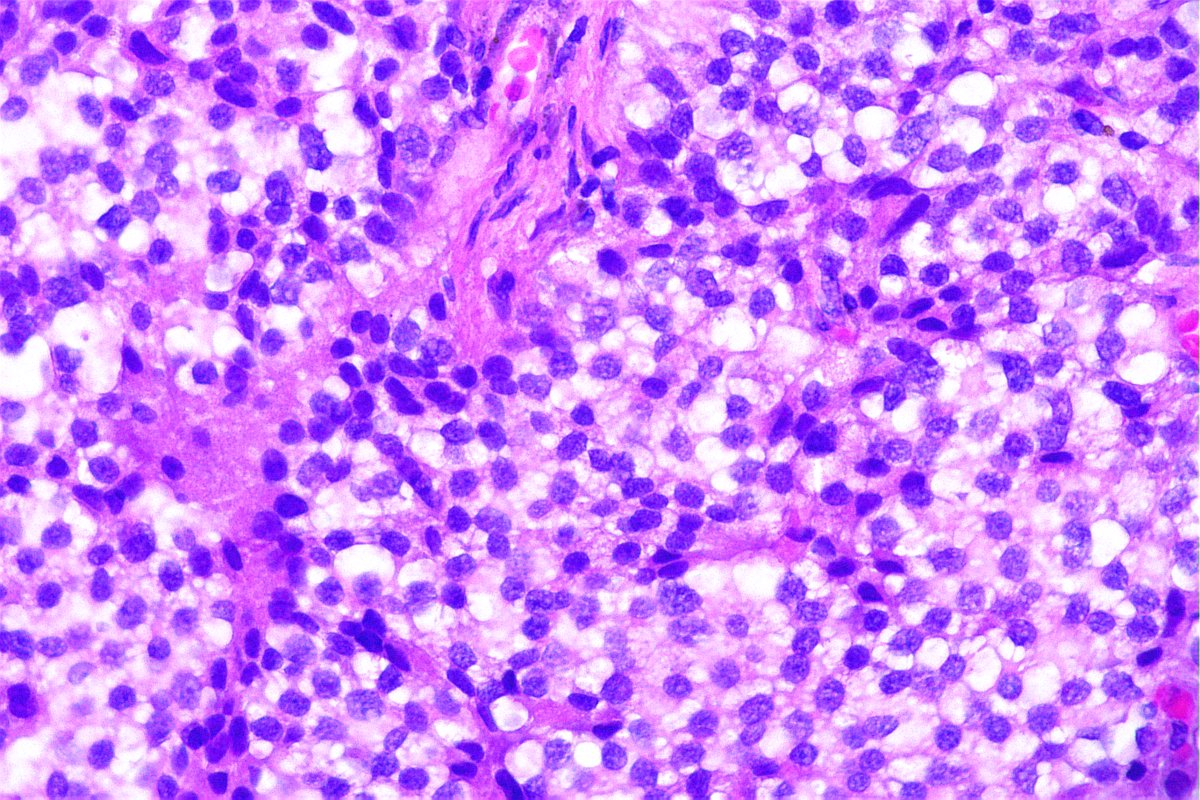

@GeronimoJrLapac

Ger么nimo Jr.

2 months

F, 47yo. The clinical information is: subepithelial lesion in the ileocecal valve. #gipath